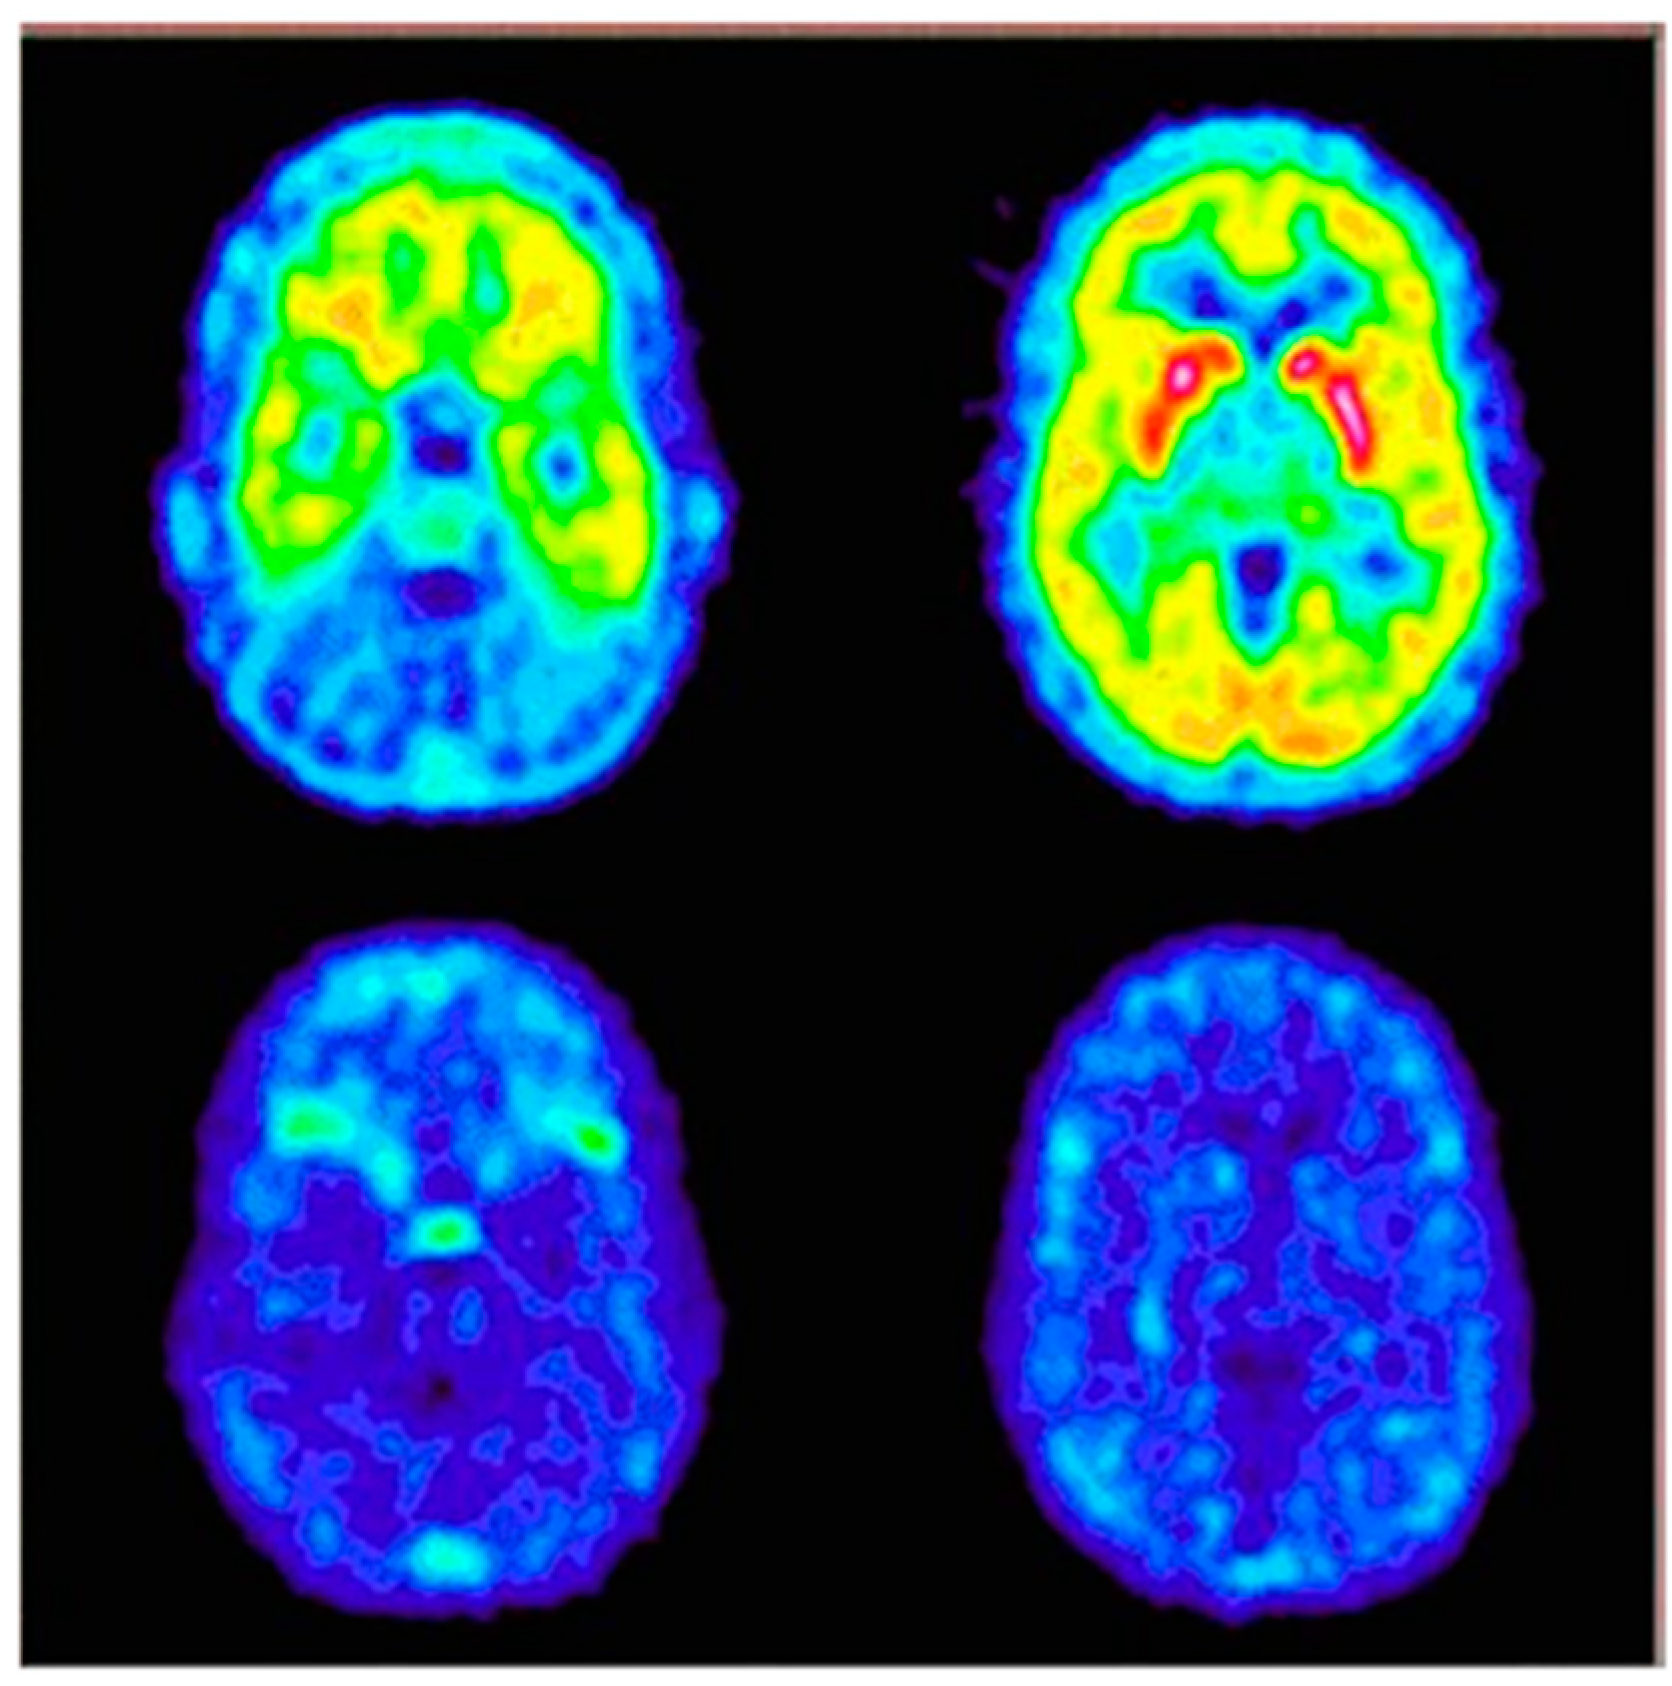

- Hietala, J.; Nyman, M.J.; Eskola, O.; Laakso, A.; Grönroos, T.; Oikonen, V.; Bergman, J.; Haaparanta, M.; Forsback, S.; Marjamäki, P.; et al. Visualization and Quantification of Neurokinin-1 (NK1) Receptors in the Human Brain. Mol. Imaging Biol. 2005, 7, 262–272. [Google Scholar] [CrossRef]

| [111In]In-DOTA-[Thi8,Met(O2)11]SP [68Ga]Ga-DOTA-[Thi8,Met(O2)11]SP | Clinical trials: used for visualisation of NK1R expression and control of radiocompound distribution at the target site and whole body; administrated simultaneously with therapeutic radiopharmaceutical [213Bi]Bi-DOTA-[Thi8,Met(O2)11]SP; | [55,127] |